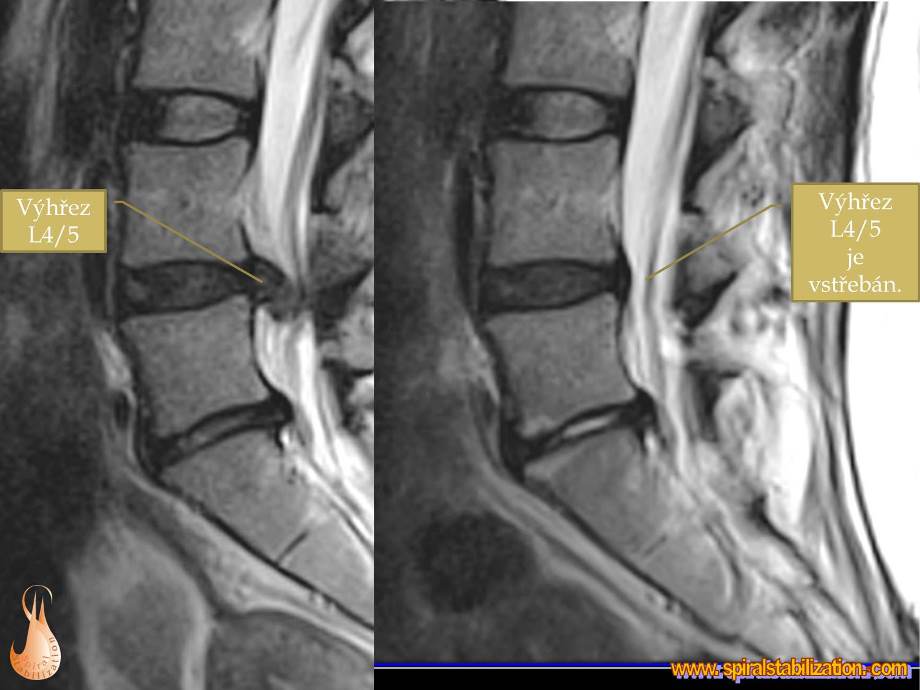

Vo väčšine prípadov dochádza k vyklenutiu platničky medzi 4. a 5. bedrovým stavcom (hernia disku L4/L5). V niektorých prípadoch môže dôjsť k vyklenutie medzi 5. bedrovým stavcom a 1. stavcom tvoriacim krížovú kosť (hernia disku L5/S1), čo sa prejavuje často poruchou citlivosti v oblasti vonkajšej strany stehna a predkolenia.

Výsledky hernia L4/L5